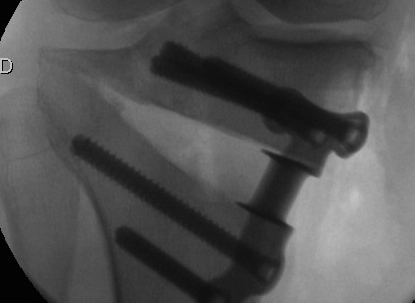

Consider lateral hinge 2 mm K wire

- 10 mm from lateral cortex

- distal to proximal

Prevention

10 mm from lateral cortex

Aim for tibio-fibular joint

Slow correction

Lateral 2 mm K wire - inserted distal to proximal 10 mm from lateral cortex

? Biplanar osteotomy

- 206 OW HTO, 71 had lateral K wire

- no K wire: hinge fracture 40%

- K wire: hinge fracture 17%